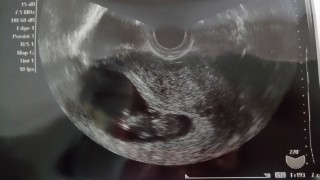

写真:10w4d:さくらさん

10w4d 大きさ42mm

2週前の検診時から、倍の大きさに。

今回は寝ているのか、じっと大人しいぼうや。心臓はトクットクッと元気に動いており、心音からも元気なのが伝わりました。先生からも順調とのお言葉をいただき安心ました。

今日のぼうやの見た目はまるで遠い星からやって来たグレイ!2週間後の検診が今からとても楽しみです。